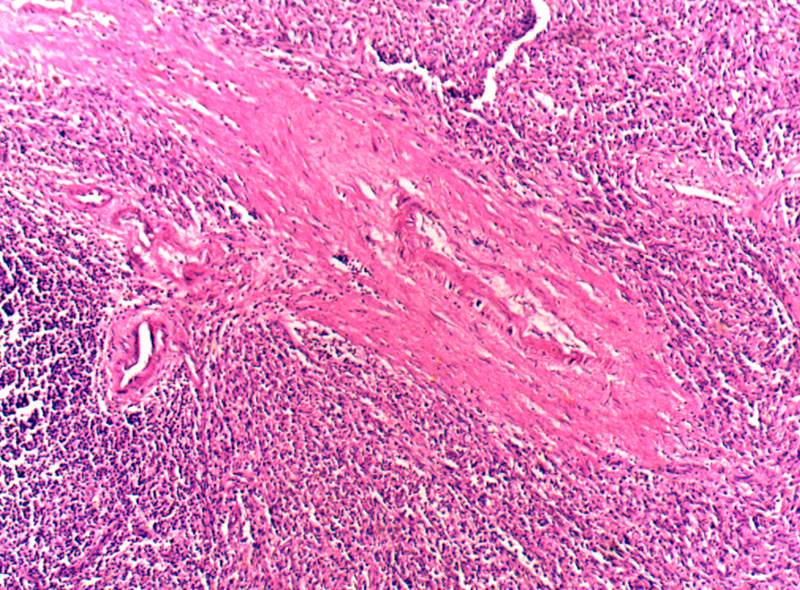

脾細(xì)動(dòng)脈玻璃樣變